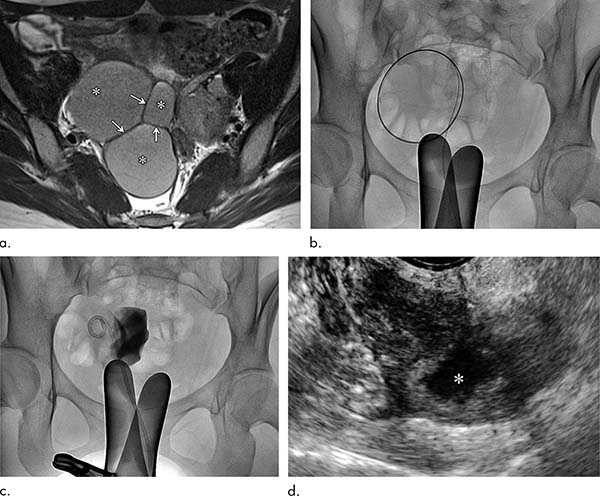

Clinical course of a 27-year-old woman with primary ovarian endometrioma presenting with dysmenorrhea. (a) Axial T2-weighted image reveals an 8.4-cm, multilocular endometrioma (∗) with internal septation (arrows). (b) The endometrioma was punctured and mechanical breakdown of the internal septa was performed. (c) A catheter was inserted and contrast agent was injected to observe for any leakage. (d) Follow-up ultrasound 6 months after catheter-directed sclerotherapy shows markedly decreased endometrioma (∗) size (1.4 cm).

The researchers evaluated catheter-directed sclerotherapy with 95 percent ethanol in 14 women between the ages of 20 and 44 with ovarian endometriomas.

After about one year, the cysts had decreased on average from 5.8 centimeters (cm) in diameter to 1.1 cm. Pain was relieved in all patients and blood tests indicated well-preserved ovarian function. There were no procedure-related complications.

There were no endometrioma recurrences, even in patients with internal septation within their cysts. In catheter-directed sclerotherapy, once the endometrioma is punctured, clinicians can manipulate the guidewire and catheter to break down internal septations, allowing for more effective treatment.